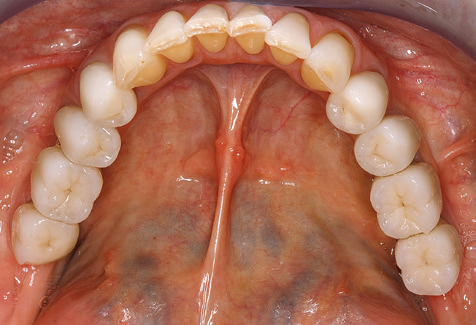

Due to the presence of periodontal disease, SPT was performed every three months in the first years following the insertion. The patient demonstrated a high degree of motivation and good compliance. The pocket depths recorded annually revealed a stable periodontal situation with a BOP index of below five per cent. On the basis of the stable periodontal situation and good cooperation on the patient’s part, the recall interval was extended to every six months as of the sixth year of the prosthetic function phase. Following the change in the recall interval, the respective annual documentation of the periodontal status continued to reveal a stable periodontal situation with no increase in the pocket depths and a BOP index below five per cent (Fig. 2a and b).

The ten-year check-up revealed no indications of advancing clinical attachment loss or peri-implant bone substance loss (Fig. 3).

Fig. 2: The pocket depths recorded annually with six-monthly SPT display no increasing trend and a BOP index of below 5 per cent with a largely inflammation-free periodontal situation. a) PERIO status in 2011 (after five years with implants). b) PERIO status in 2016 (after ten years with implants).